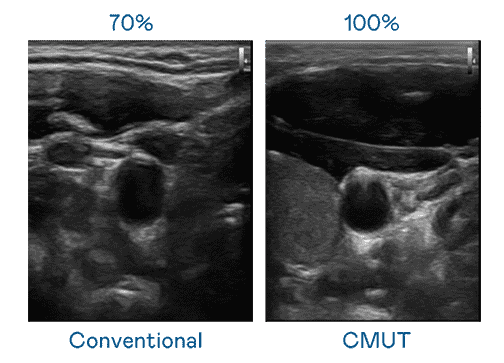

CMUT 技术是一种用电容式微机电元件来产生超音波讯号的技术。。。与传统 PZT 压电式技术相比,,,CMUT 频宽增加 30%,,,,更宽频的超音波讯号让影像解析度大幅提升,,,是实现高影像品质医疗超音波扫描、、、促进精准医疗发展的关键技术。。。。

大频宽带来超清晰影像

超音波影像的解析度高低,,首先取决于探头能发出的讯号频宽。。。尊龙z6 CMUT 可提供高清晰的超音波讯号,,,,提供高频宽、、、高灵敏度、、影像纹理细节更高的超音波影像,,,协助医护人员缩短影像判读时间及利用精准的医疗影像进行诊断。。。。